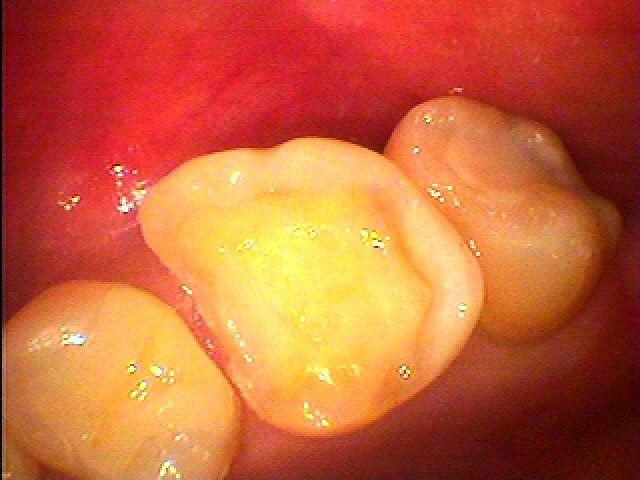

銀歯をすべてセラミックへやり変えていきます セラミックを用いた臨床例 審美治療|お知らせ |広島市安佐南区の歯科医院 銀歯をすべてセラミックへやり変えていきます セラミックを用いた臨床例 審美治療 トップ お知らせ・ブログ お知らせ 銀歯をすべてセラミックへやり変えていきます セラミックを用いた臨床例 審美治療 銀歯をすべてセラミックへやり変えていきます セラミックを用いた臨床例 審美治療 左上の6番部になります この銀歯を外して虫歯治療を行っていきます 中はこのようになっていました 近心部の虫歯を除去していきました CR樹脂にて覆罩を行っています セレックセラミックにて修復しています 銀歯が外れたとのこと わずかに虫歯が存在していました セレックセラミックにて修復しています 綺麗に仕上がりました Web診療予約 初めての方へ 選ばれ続ける理由 院内設備について 歯が痛いしみる一般歯科 歯がぐらぐらする歯周病 健康な歯を保ちたい予防歯科 子供の虫歯予防をしたい小児歯科 銀歯をセラミックに審美歯科 白い歯を目指しませんか?ホワイトニング 矯正専門医がいるので安心矯正歯科 抜けた歯を補いたいインプラント・入れ歯 医院案内 スタッフ紹介 メリィハウス歯科クリニックオフィシャルホームページ ラベンダー歯科クリニックオフィシャルホームページ お知らせ・ブログ ホーム 診療科目 一般歯科 歯周病治療 予防治療 小児歯科 審美治療 ホワイトニング 矯正歯科 入れ歯・インプラント マウスピース矯正 初めての方へ 院長・スタッフ 設備紹介 医院案内・アクセス メニューを閉じる